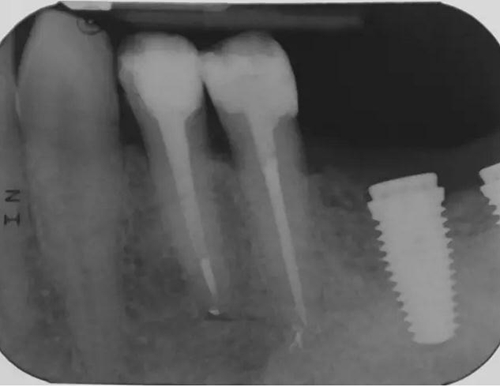

圖6 左下4和左下5使用瓷納美通用修復(fù)型樹脂及SDR修復(fù)后的效果。

圖7 術(shù)后片。左下4重新疏通。根尖4mm牙膠封閉,根管內(nèi)粘結(jié)了纖維樁。左下5根尖有根分叉。在根管冠段,可以樹脂(SDR)進(jìn)入,輔助固位。